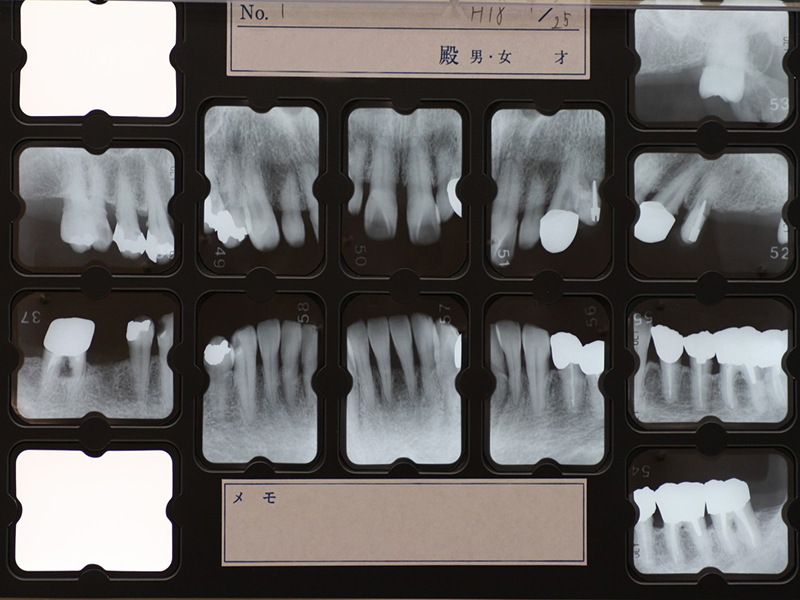

初診時X線写真